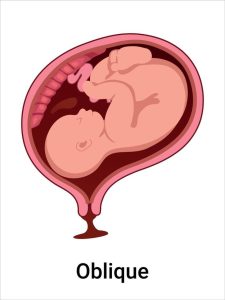

Oblique Lie (Umwana yicaye mu buryo buteruye)

Nk’uko tubibonye hejuru, mu bisanzwe umwana aba yicaye mu nda ku murongo uhuza umutwe n’ikibuno (longitudinal lie). Ariko hari igihe umwana aticara neza, akicara mu buryo bita oblique lie:

– Icyo bivuze: Umwana aba yicaye mu nda mu buryo buteruye, atari ku murongo uhuza umutwe n’ikibuno (longitudinal), kandi atari ku ruhande rwose (transverse). Ni nko kuba umutwe we uri mu gice kimwe cy’inkondo y’umura, ikibuno kikaba kiri mu gice cy’inyababyeyi hejuru, ku buryo umwana aba “ateruye” mu nda.

– Ingaruka:

– Kubyarira mu buryo busanzwe bigorana cyane, kuko inkondo y’umura iba itabonye umutwe cyangwa ikibuno neza.

– Umwana ashobora guhindura umwanya mu gihe cy’ibise, ariko iyo akomeje kuguma muri oblique lie, akenshi bisaba kubagwa (cesarean section).